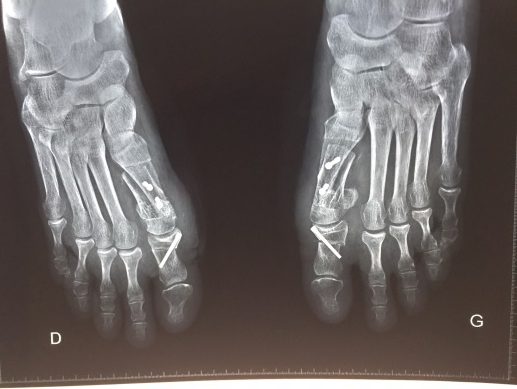

Quelques exemples avec vis intra-articulaire, raccourcissement du gros orteil avec métatarsiens latéraux trop longs, absence de correction de l’angle inter-métatarsien.

- une vis trop longue gênant le chaussage, ou intra-articulaire. On conseille, par ailleurs, de ne pas retirer le matériel au niveau du membre inférieur avant 12 à 18 mois.

- un raccourcissement trop important de l’hallux avec douleurs déportées sur les têtes de métatarsiens latéraux.

- une récidive à distance (souvent ostéotomie insuffisante de redressement du premier métatarsien).